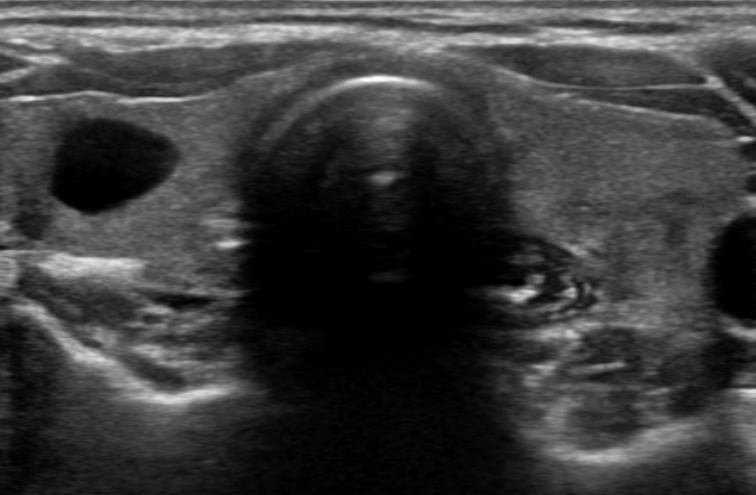

요즘 갑상선에 대한 영상 검사, 특히 초음파 검사를 많이 하게 되면서, 갑상선 낭종을 발견하는 경우가 늘어났습니다. 낭종이라는 어려운 용어를 들으면 문득 겁이 나거나 당황스러울 수 있지만, 사실 갑상선 낭종은 암과는 관련성이 크지 않은 경우가 대부분입니다.

갑상선 안에 물 같은 액체로 채워진 주머니 모양의 구조물이며, 쉽게 말해 갑상선에 있는 물집이라고 생각하면 되겠습니다. 그러나 갑상선 낭종은 때때로 고체 성분을 포함하는 경우도 있는데 이런 경우에는 드물게 암과 관련이 있는 경우도 있기 때문에 관리 및 추적검사가 필요합니다.

갑상선 낭종의 진단에는 주로 초음파 검사가 사용됩니다. 초음파는 방사선 노출이 없고 안전하기 때문에 널리 활용됩니다.

1) 초음파 검사: 낭종의 위치, 크기, 내부 구조를 파악합니다.